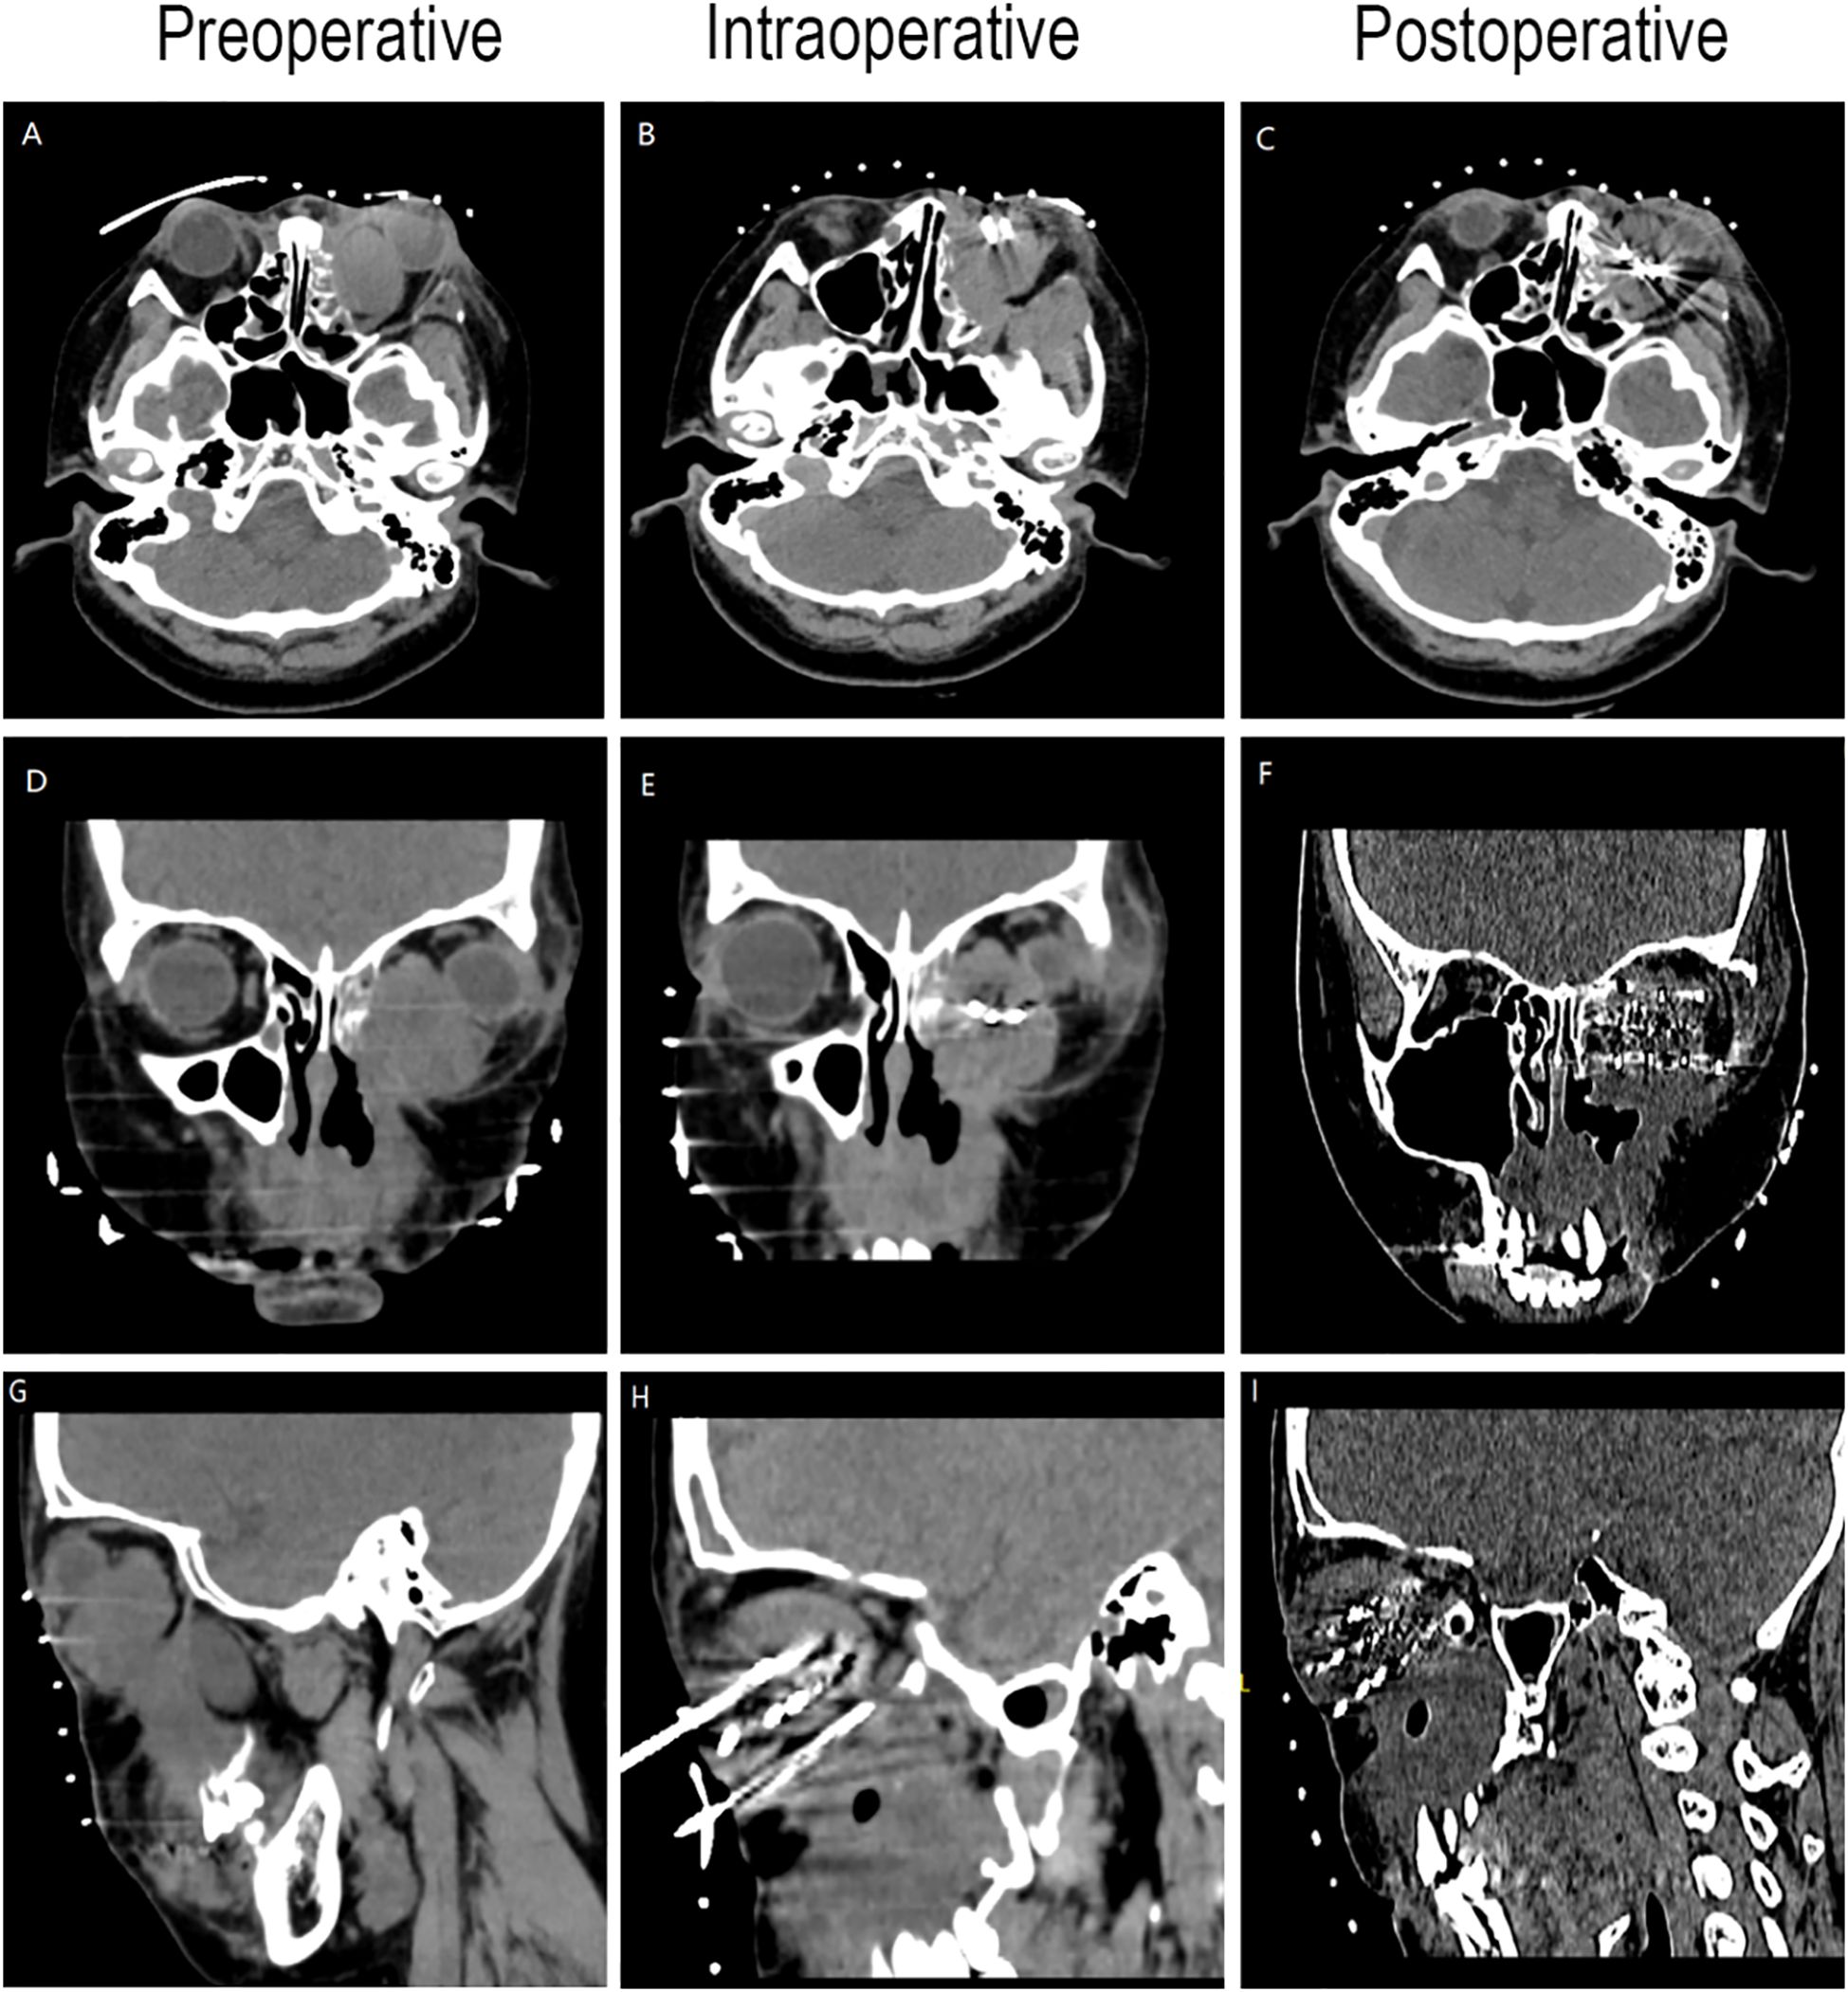

Preoperative Pathological Diagnosis confirmed Low-Grade Myxofibrosarcoma (left maxillary sinus) with spindle cell morphology, fibrous histiocytoma-like architecture (Figure 3), and myxoid degeneration. Immunohistochemistry showed Vimentin (+), SATB2 (+), MDM-2 (+), and Ki-67 (+30%). Considering the patient’s treatment history and the limitations of the anatomical structure, we proposed the use of Iodine-125 particle implantation therapy. Given the unique location of the tumor (which directly invaded the orbital region and compressed the optic nerve), this form of brachytherapy inherently carries the risk of optic nerve and retinal damage, presenting a significant clinical challenge. Prior to the surgery, we extensively reviewed a large number of relevant studies and planned the surgical procedure using the Treatment Planning System (TPS)to ensure the scientific basis of the surgical plan and to minimize the safety risks to adjacent organs (such as the optic nerve) (10, 11). Based on the patient’s tolerable surgical duration, the treatment was divided into two stages. Preoperative TPS planning guided precise implantation of radioactive seeds before each procedure (Supplementary Figures 1, 2). A total of 197 I-125 seeds (0.3 mCi/seed) were implanted to deliver a total prescription dose of 12,000 cGy (Stage 1: 71 seeds, Stage 2: 126 seeds). The initial surgery was performed in March 2024 (Figure 4). Postoperative CT-based TPS dosimetric evaluation confirmed high concordance between the spatial distribution/dosimetry of implanted I-125 seeds and preplanned configurations (Supplementary Figures 3, 4). The preceding description summarizes the patient’s core clinical profile (Table 1). All treatment plans were generated using the domestic Fei Tian Program TPS, with its specialized Fei Tian Brachy v3.00.00 module for brachytherapy planning.

Figure 4. CT-guided iodine-125 seed implantation. (A–C) Axial CT image. (D–F) Coronal CT image. (G–I) Sagittal CT image.